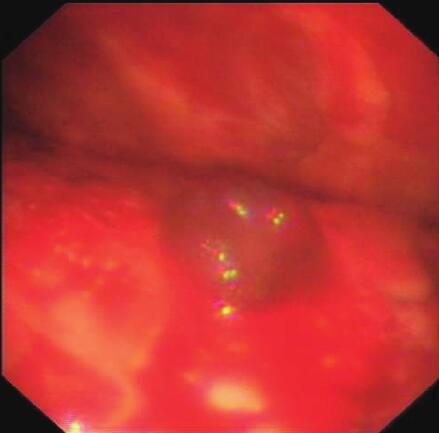

七、内科胸腔镜检查结果

内科胸腔镜下见壁层及脏层胸膜多发充血结节,大小不等,胸膜增厚,局部有粘连(图4)。病理结果显示:恶性胸膜间皮瘤(肉瘤型)。至此诊断明确,为恶性胸膜间皮瘤(肉瘤型)。

图4